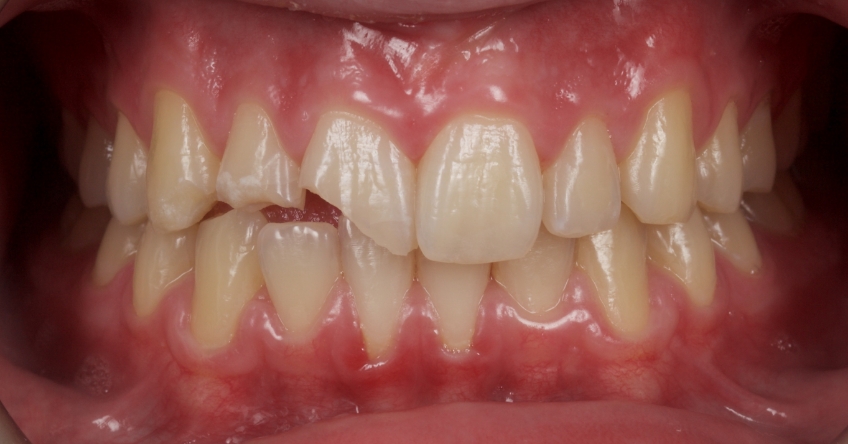

This 21-year-old male presented with an uncomplicated enamel-dentin fracture of the upper right central, lateral incisor, and canine following a fall.